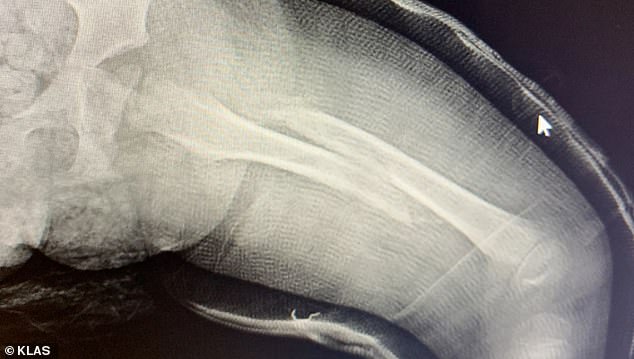

Shortly after, he and his wife learned their son’s leg was broken. The family provided an X-ray to the network.